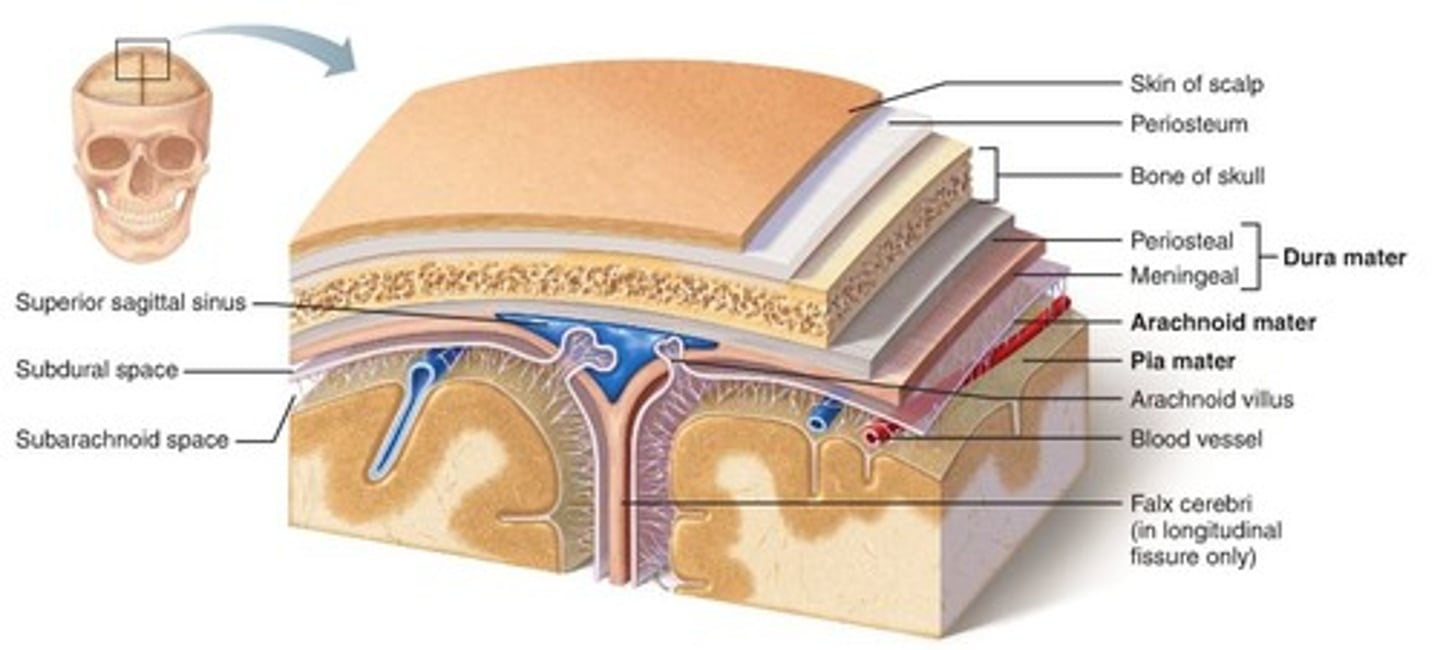

meninges

scalp, periosteium, then, 1st meningeal layer. Includes dura mater, arachnoid mater, and pia mater.

dura mater

2 layers. Periosteal layer (outer layer) and the meningeal layer - closest to next meningeal layer. This can create the dural venous sinus. right below 1 in this picture

arachnoid mater

meningeal layer on top. 2 in this picture

pia mater

sits directly on top of brain tissue. When CSF circulates, it circulates on top of brain tissue. If you try to tear pia mater away, you'll tear brain tissue. 3 in this picture